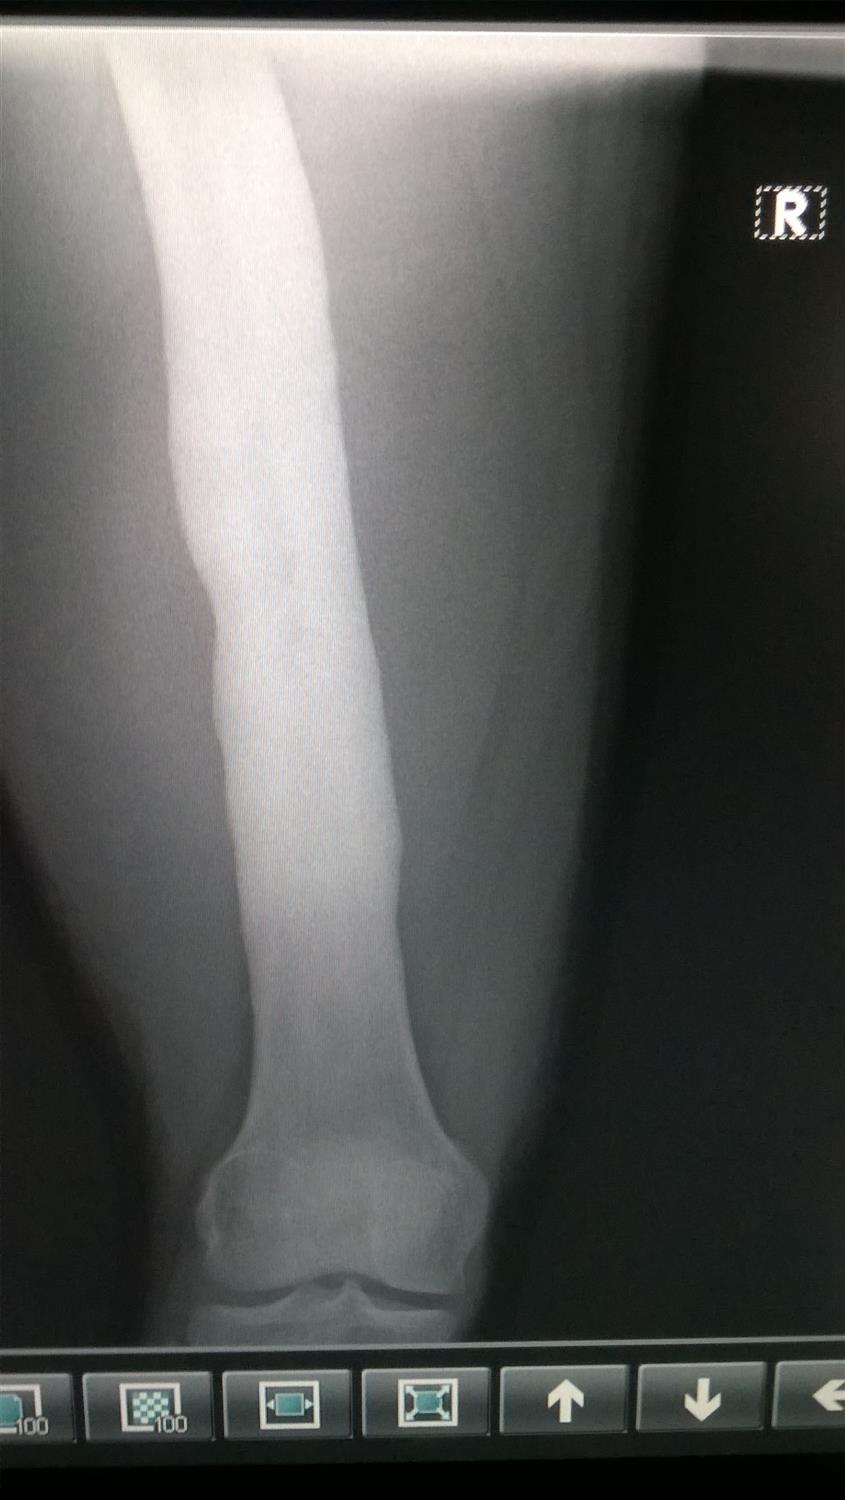

Typical radiographs of chronic osteomyelitis of the tibia treated with Osteomyelitis Radiographs A plain radiograph should always be obtained first. Inhomogeneous osteosclerosis and/or sequestrum formation (necrotic bone) is. radiographic imaging is useful for diagnosing osteomyelitis, delineating the extent of disease, and planning therapy. flow chart for imaging modality choice in osteomyelitis. While plain films can identify bone. Ulceration of the soft tissues will not. plain radiography is the typical. Osteomyelitis Radiographs.